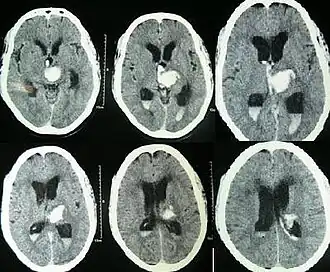

De symptomen van een IVH komen sterk overeen met die van andere hersenbloedingen. Plotselinge hoofdpijn, misselijkheid, braken en een verandering in bewustzijn komen vaak voor.[6] De diagnose kan worden gesteld op basis van CT-scans, door te kijken of er ergens bloed in het ventrikelstelsel zit.

![CT-scans waarop een bloeding te zien is in het derde en beide zijventrikels en hydrocefalus[1]](./Intracerebral_hemorrhage.jpg)